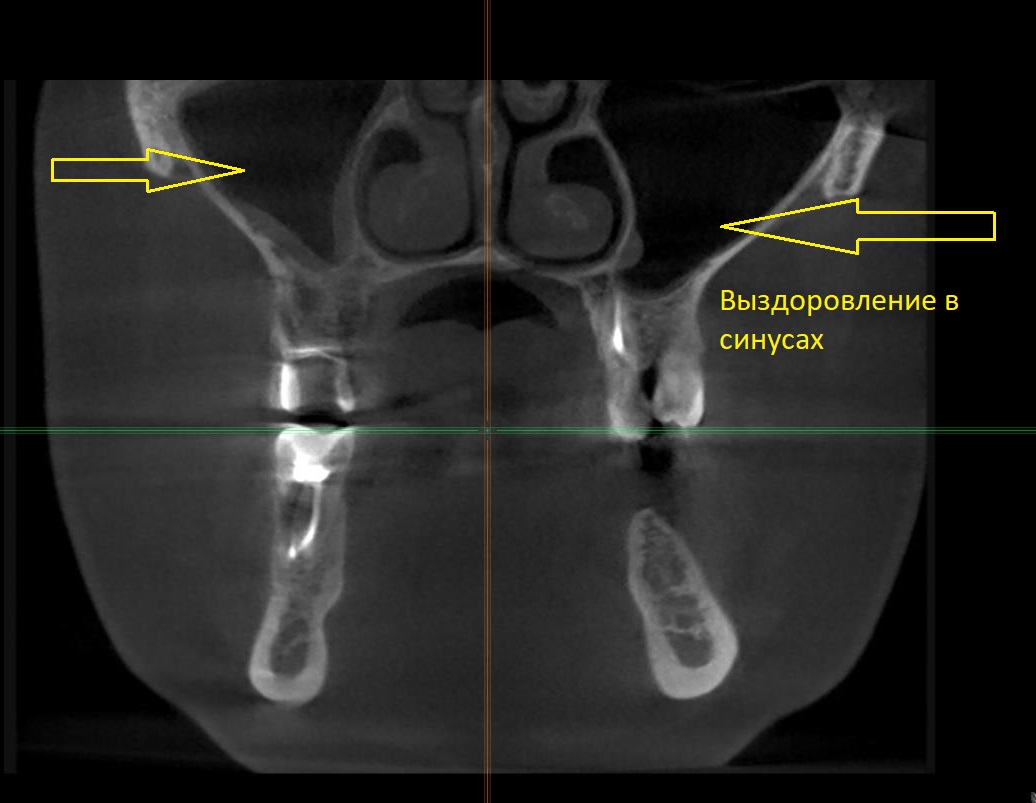

Нами было проведено повторное эндодонтическое лечение проблемных зубов.Через 6 месяцев видны отличные результаты заживления воспалительных изменений на верхушках корней, а также устранение воспаления в верхнечелюстной пазухе( гайморита).

Не спешите удалять проблемные зубы: вполне вероятно, что при грамотном лечении есть большие шансы их сохранить, а свой зуб служит ни как не меньше самого искусно установленного имплантата.